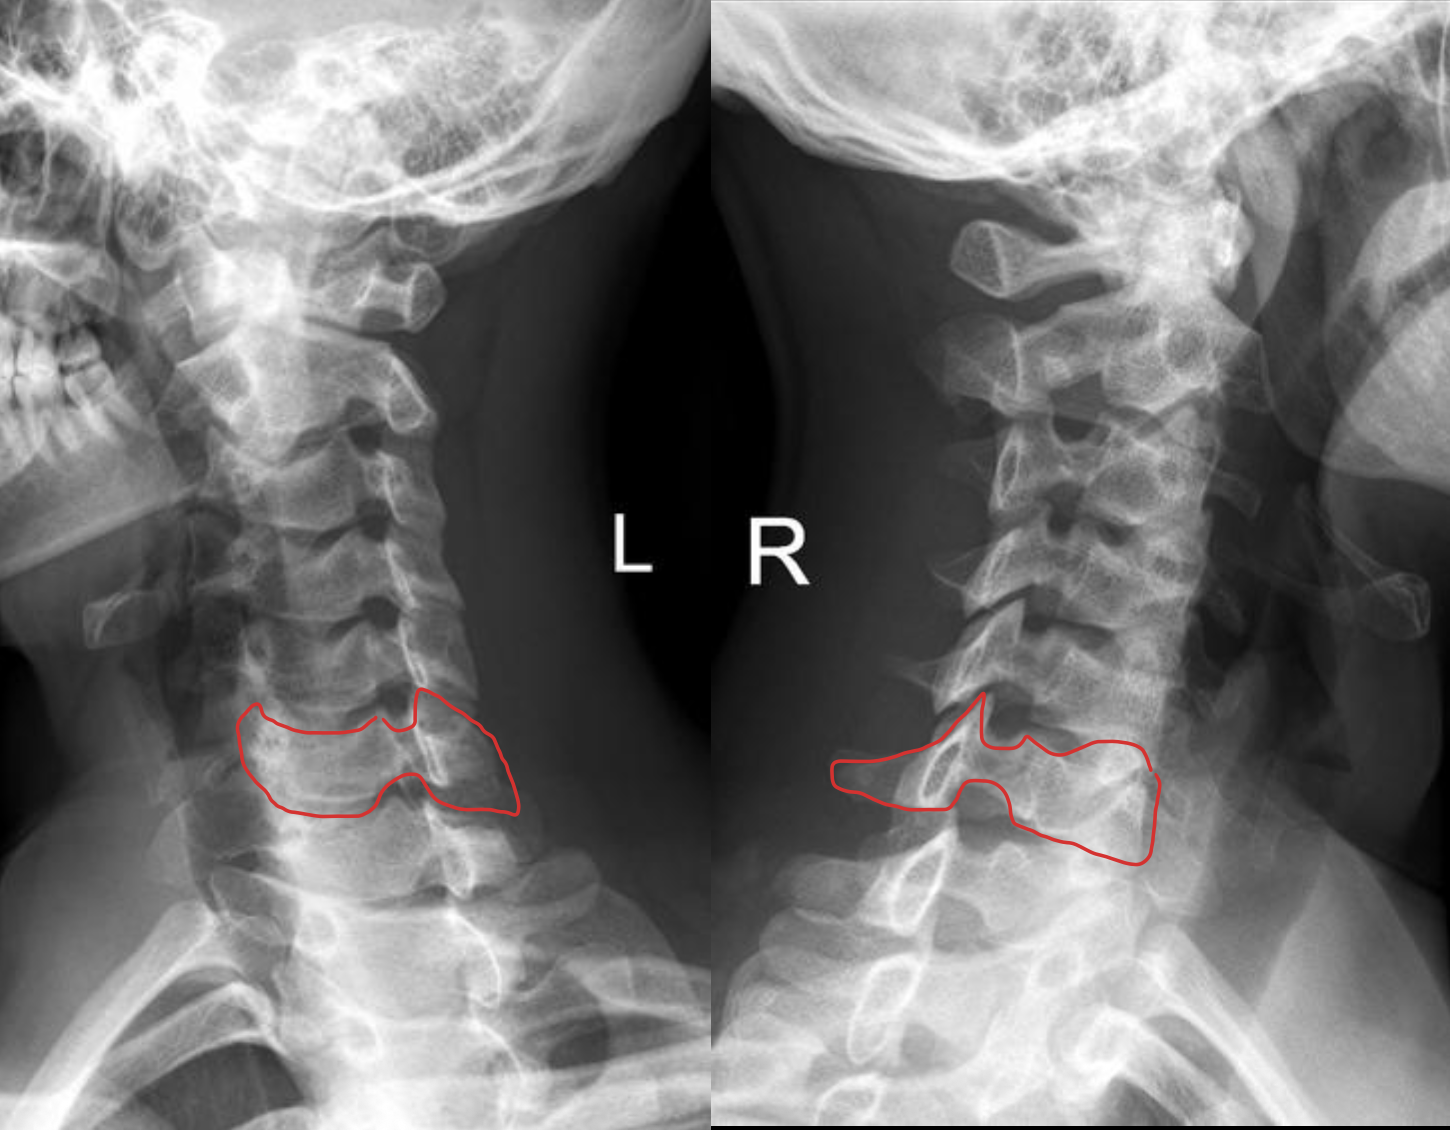

c5